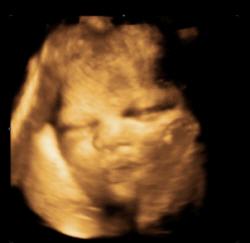

Aufnahmen aus der 16. Schwangerschaftswoche. Die Scheitel-Steiß-Länge beträgt ca. 9,4cm. |